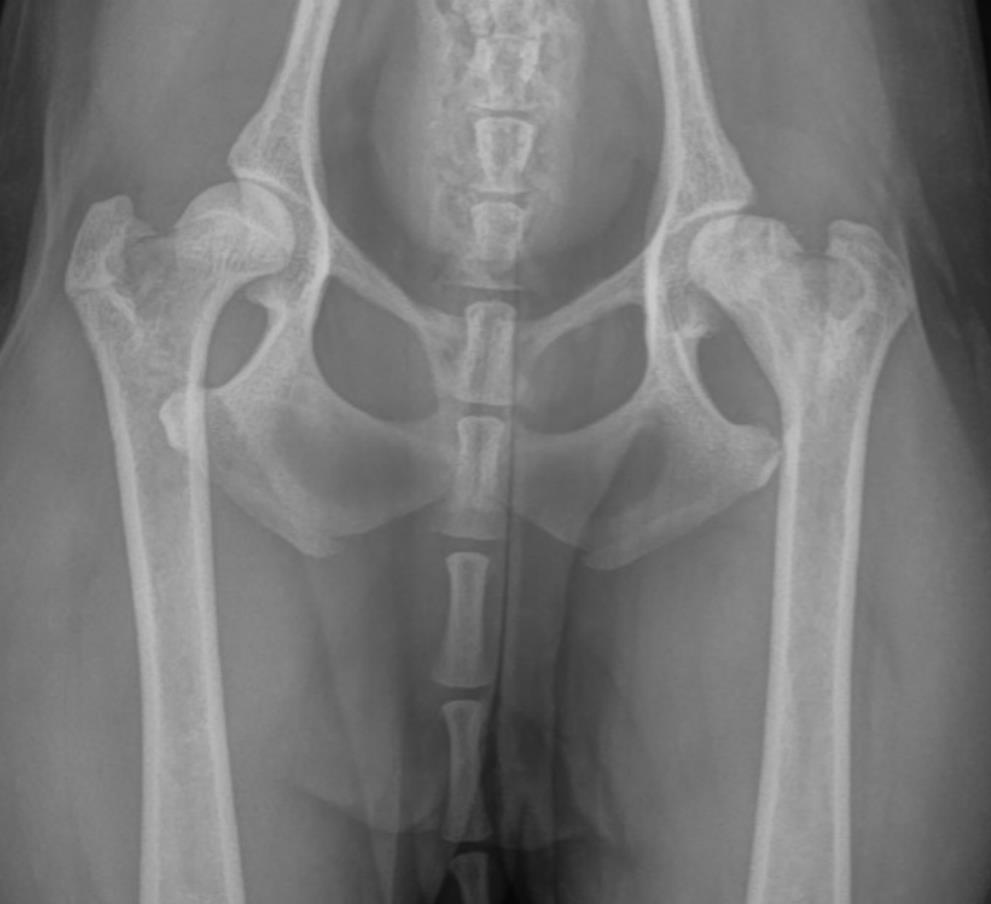

IMAGE ONLY WITH CAPTION - Pre-operative VD radiograph of the hips showing bone loss, osteolysis and a severely misshapen left femoral head.Microscopic Description:

The gross and microscopic pathology varies depending on the chronicity of the disease at the time of diagnosis.1,3 Early on, the shape and structure of the femoral head are grossly and radiographically normal. Histologically, there may be evidence of osteonecrosis predominantly within the subchondral bone at this stage.1 With chronicity, if the area of necrosis is large enough, the necrotic bone collapses which causes flattening of the femoral head (Figure 1) which eventually results in a degenerative arthropathy.1,3